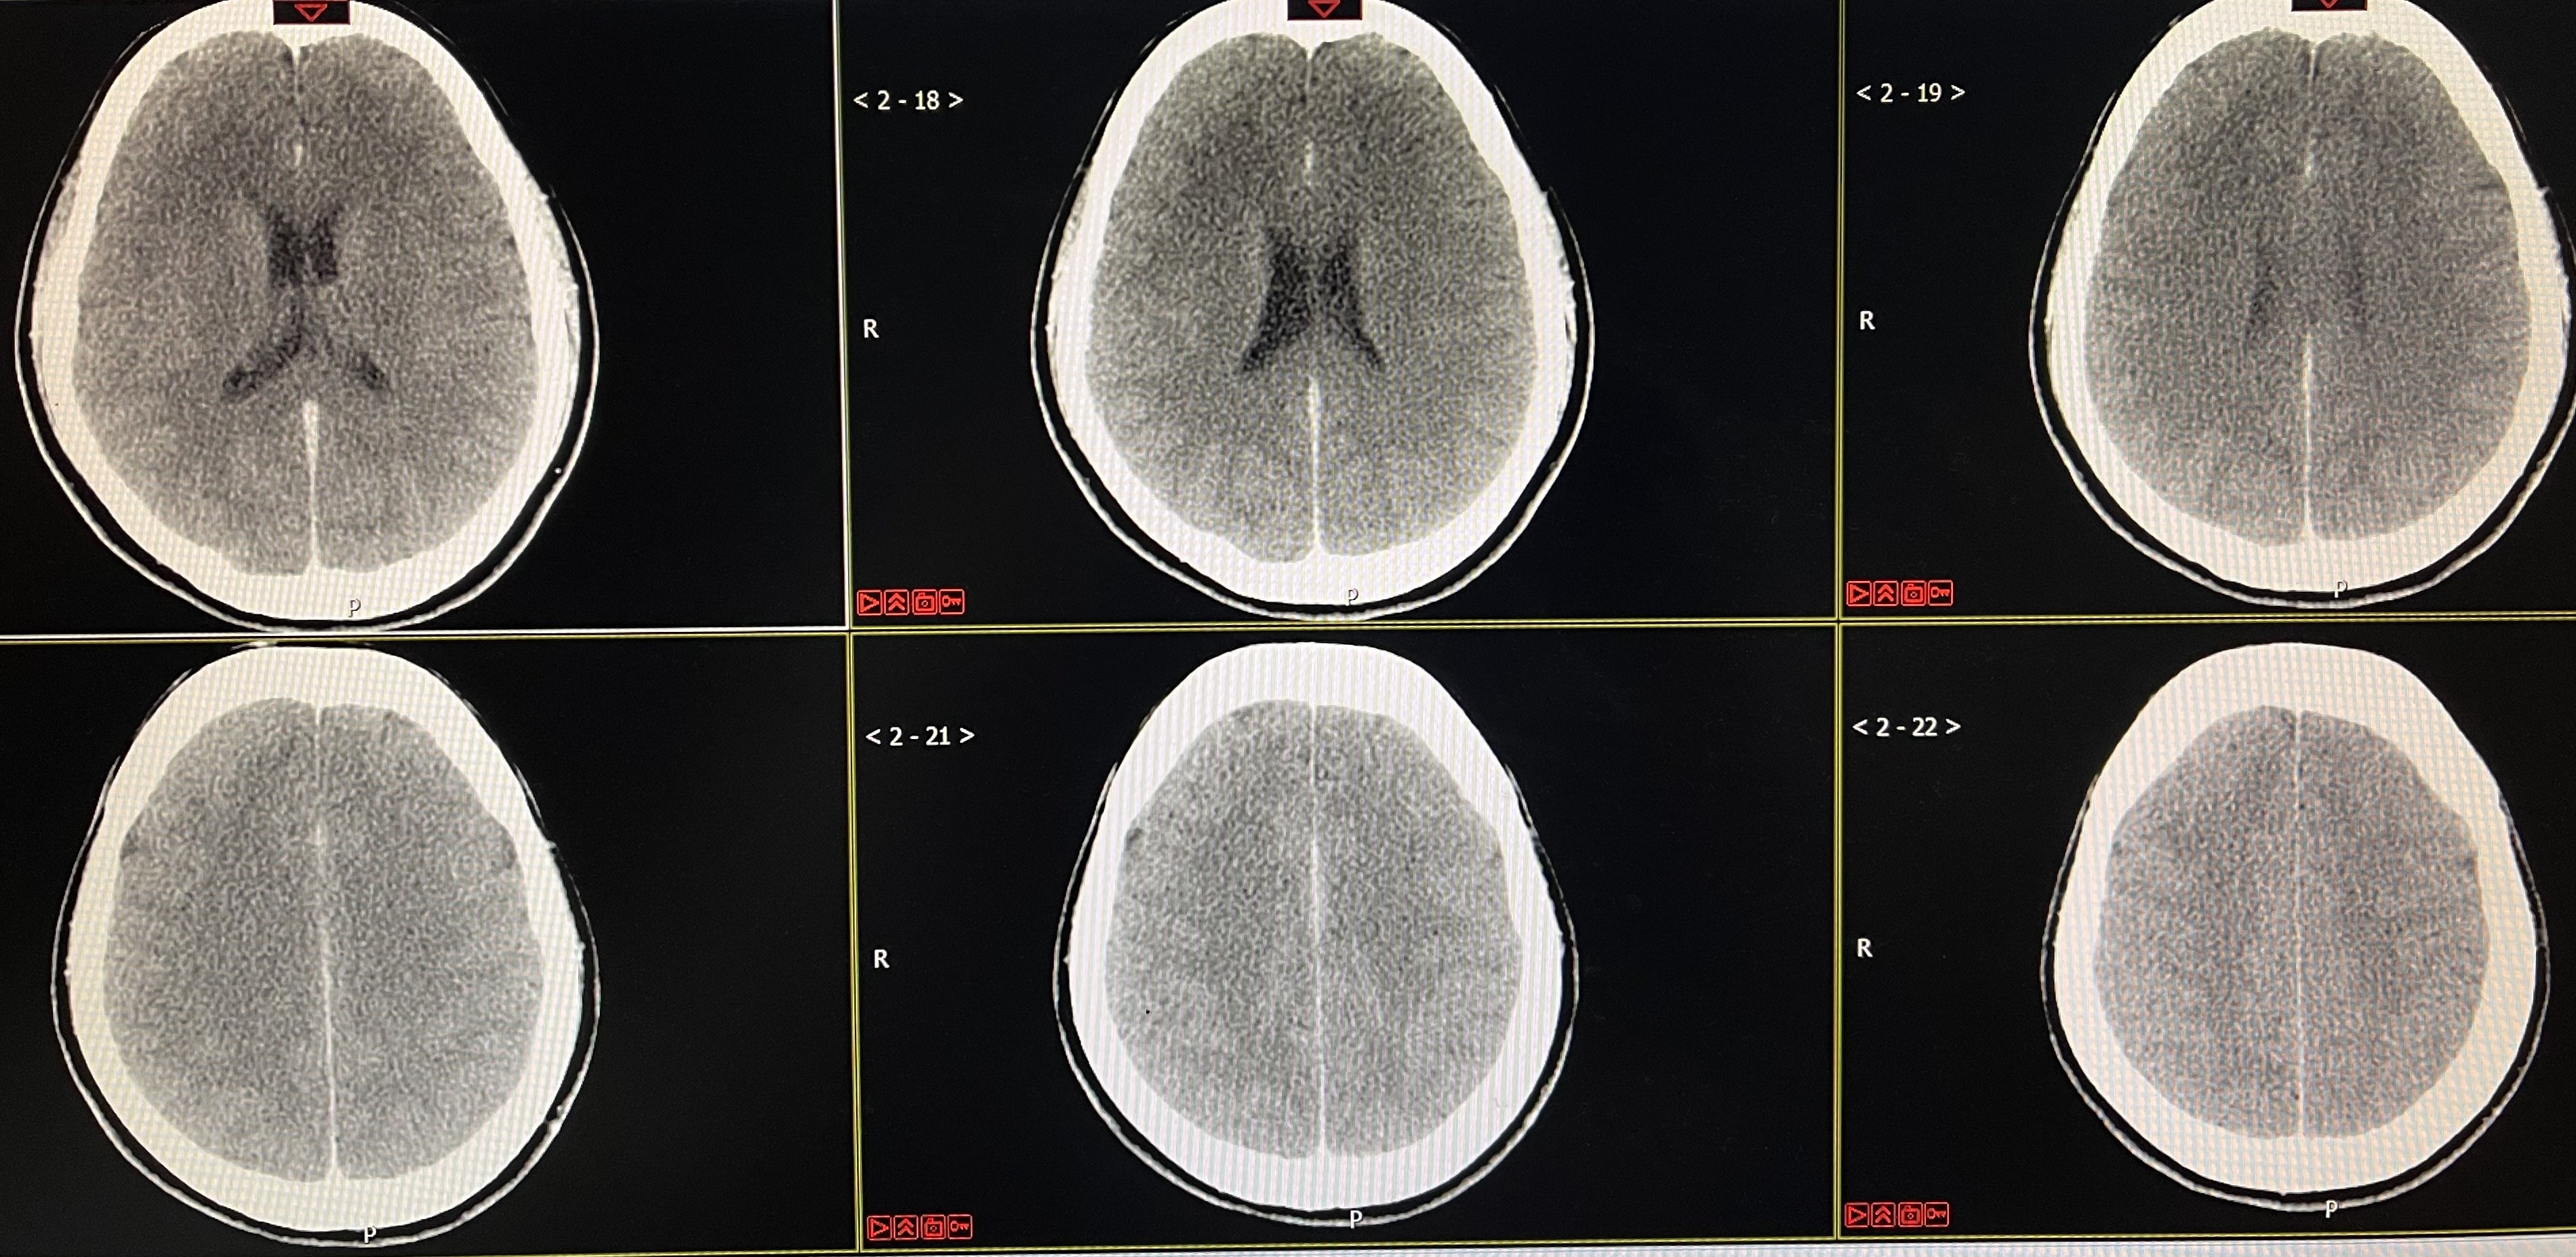

术后即刻CT